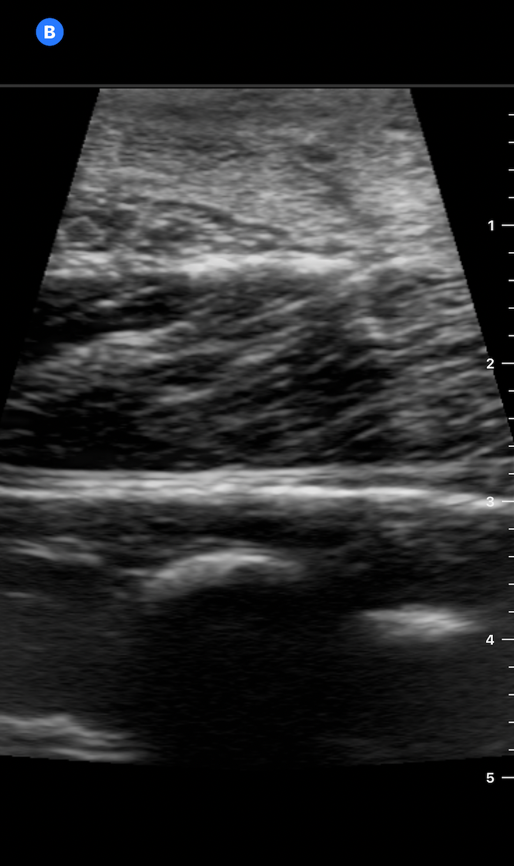

NerveBlock-Image2 Aug2024.pngImage 2. Meat model on POCUS

We found that the polenta appeared denser on POCUS than the tofu block, but the string cheese appeared similar to the tofu block, and the needle was easy to visualize in-plane. (Image 6) An injection was performed, and while it did not significantly affect visualization of structures on the phantom, it also did not show significant hydrodissection.